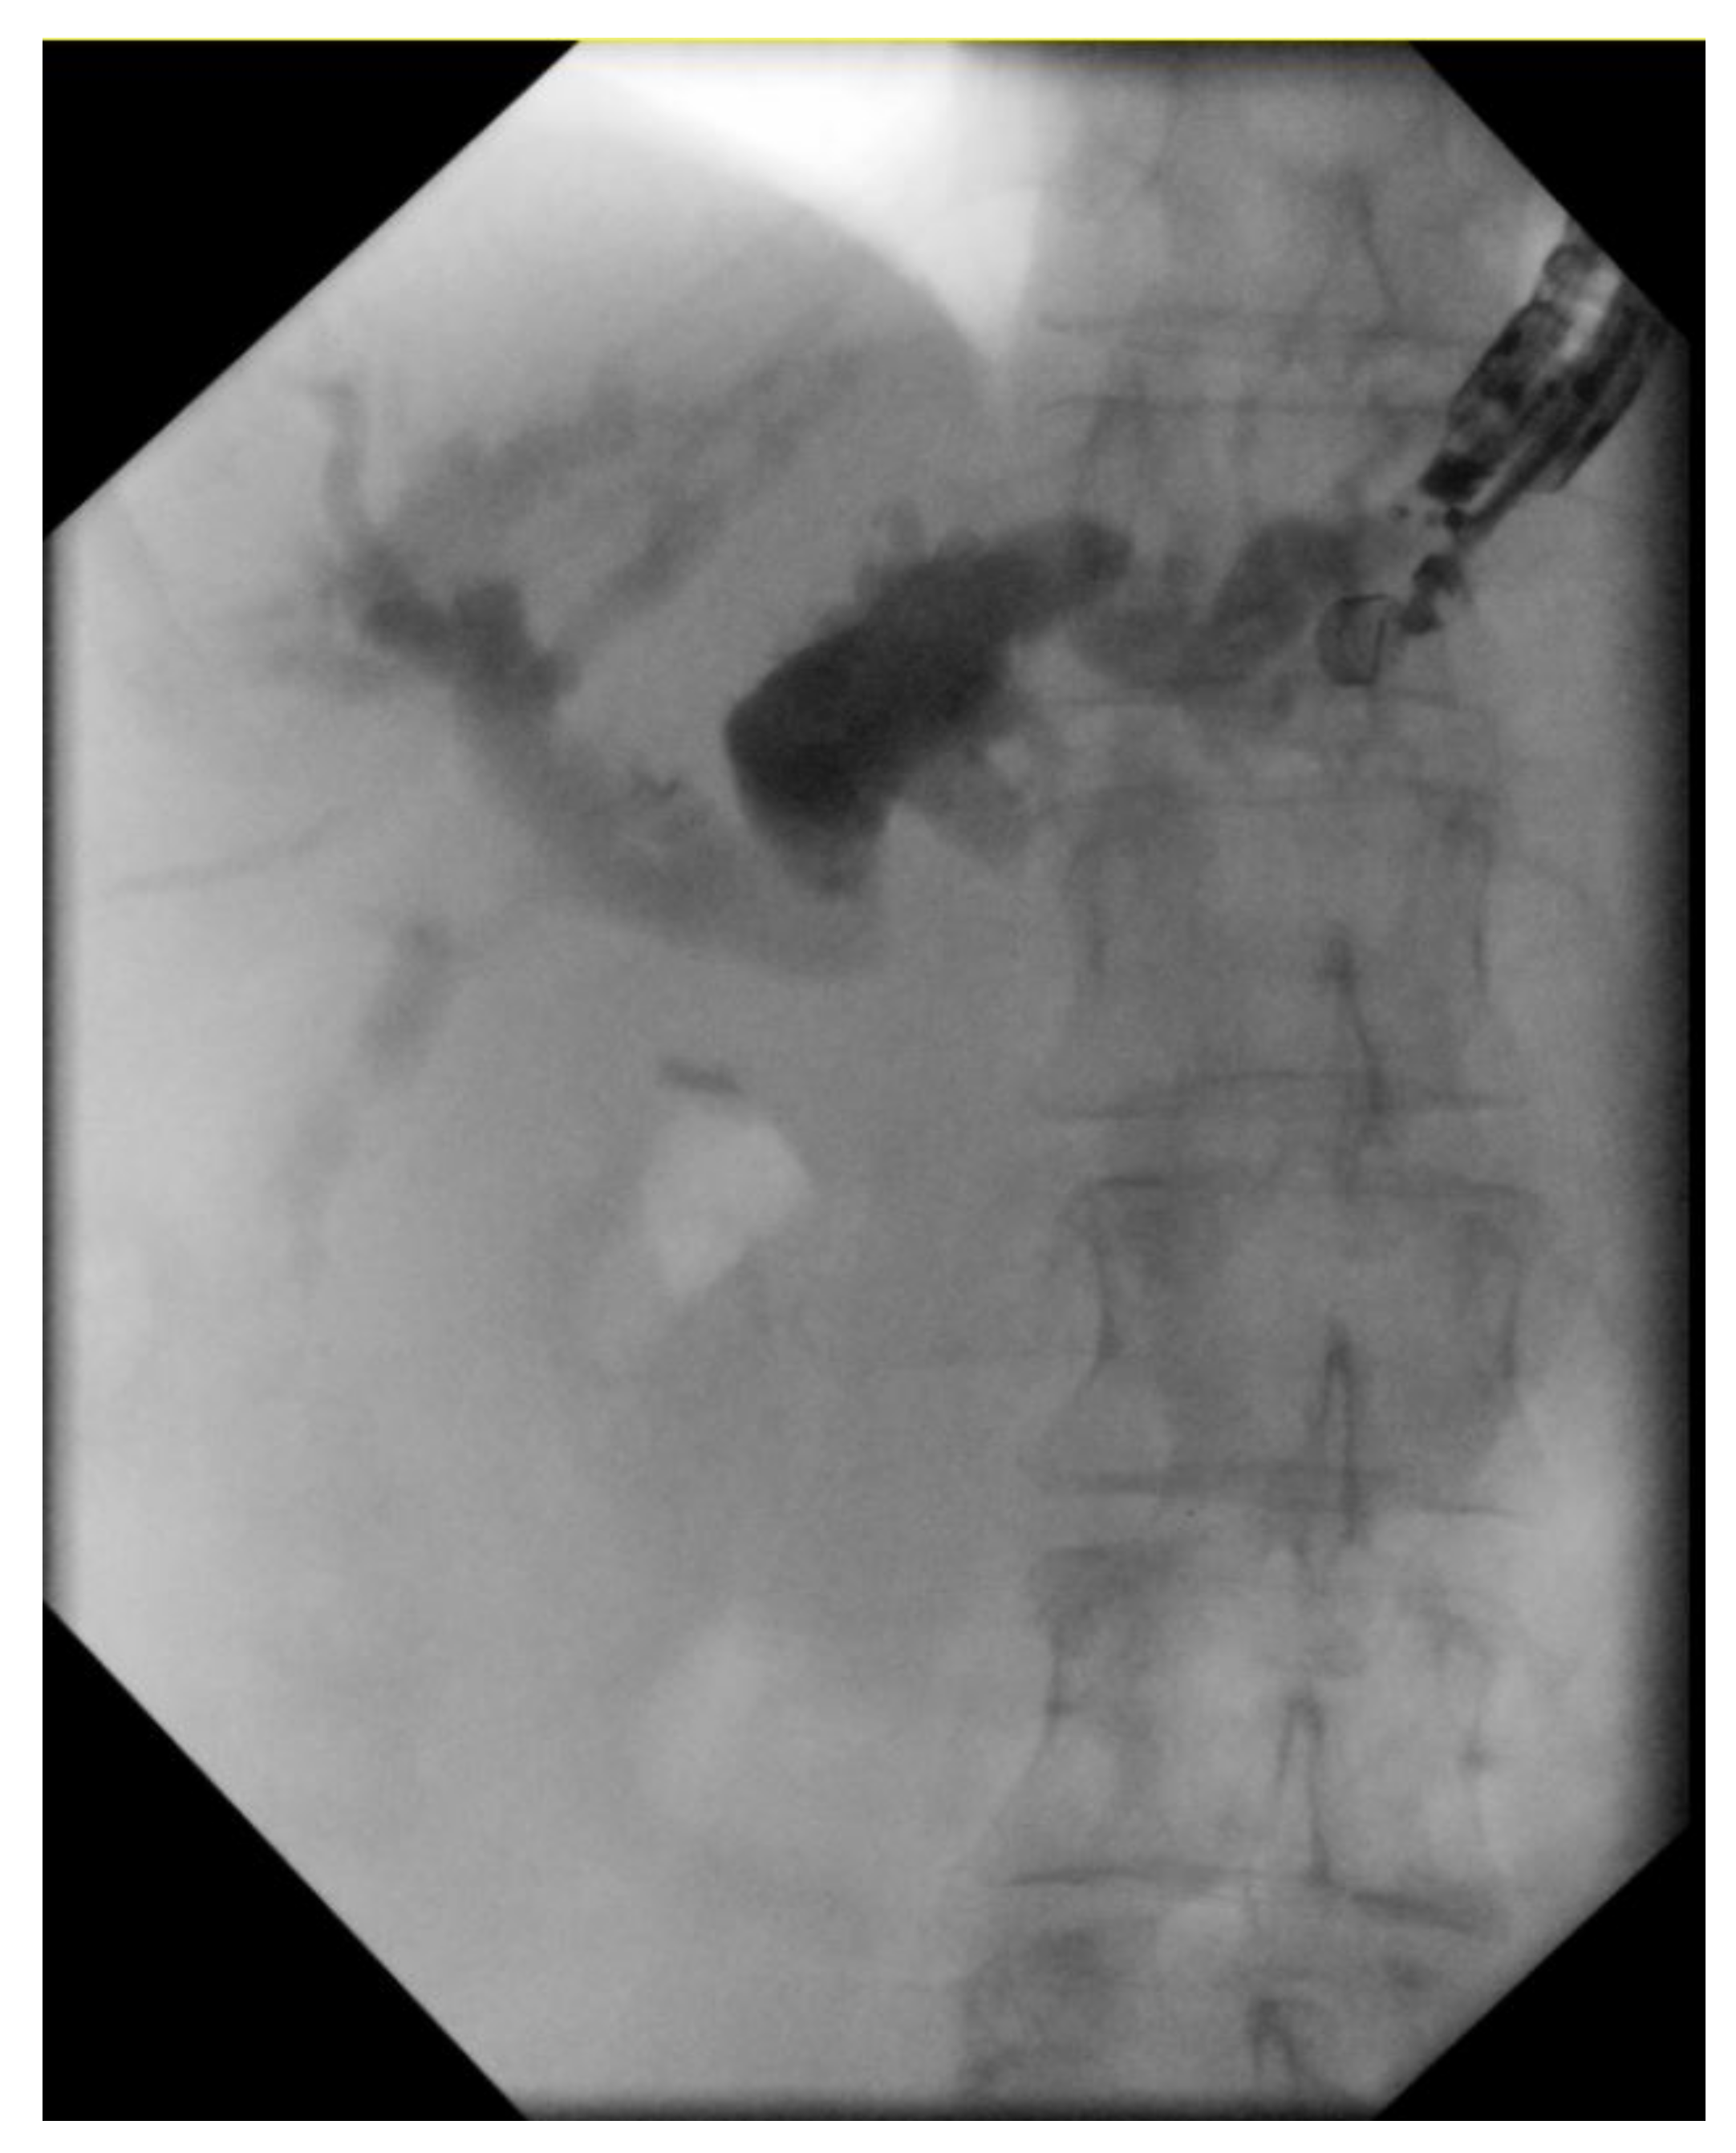

4.2. Biliary Obstruction: ERCP vs. EUS-BD